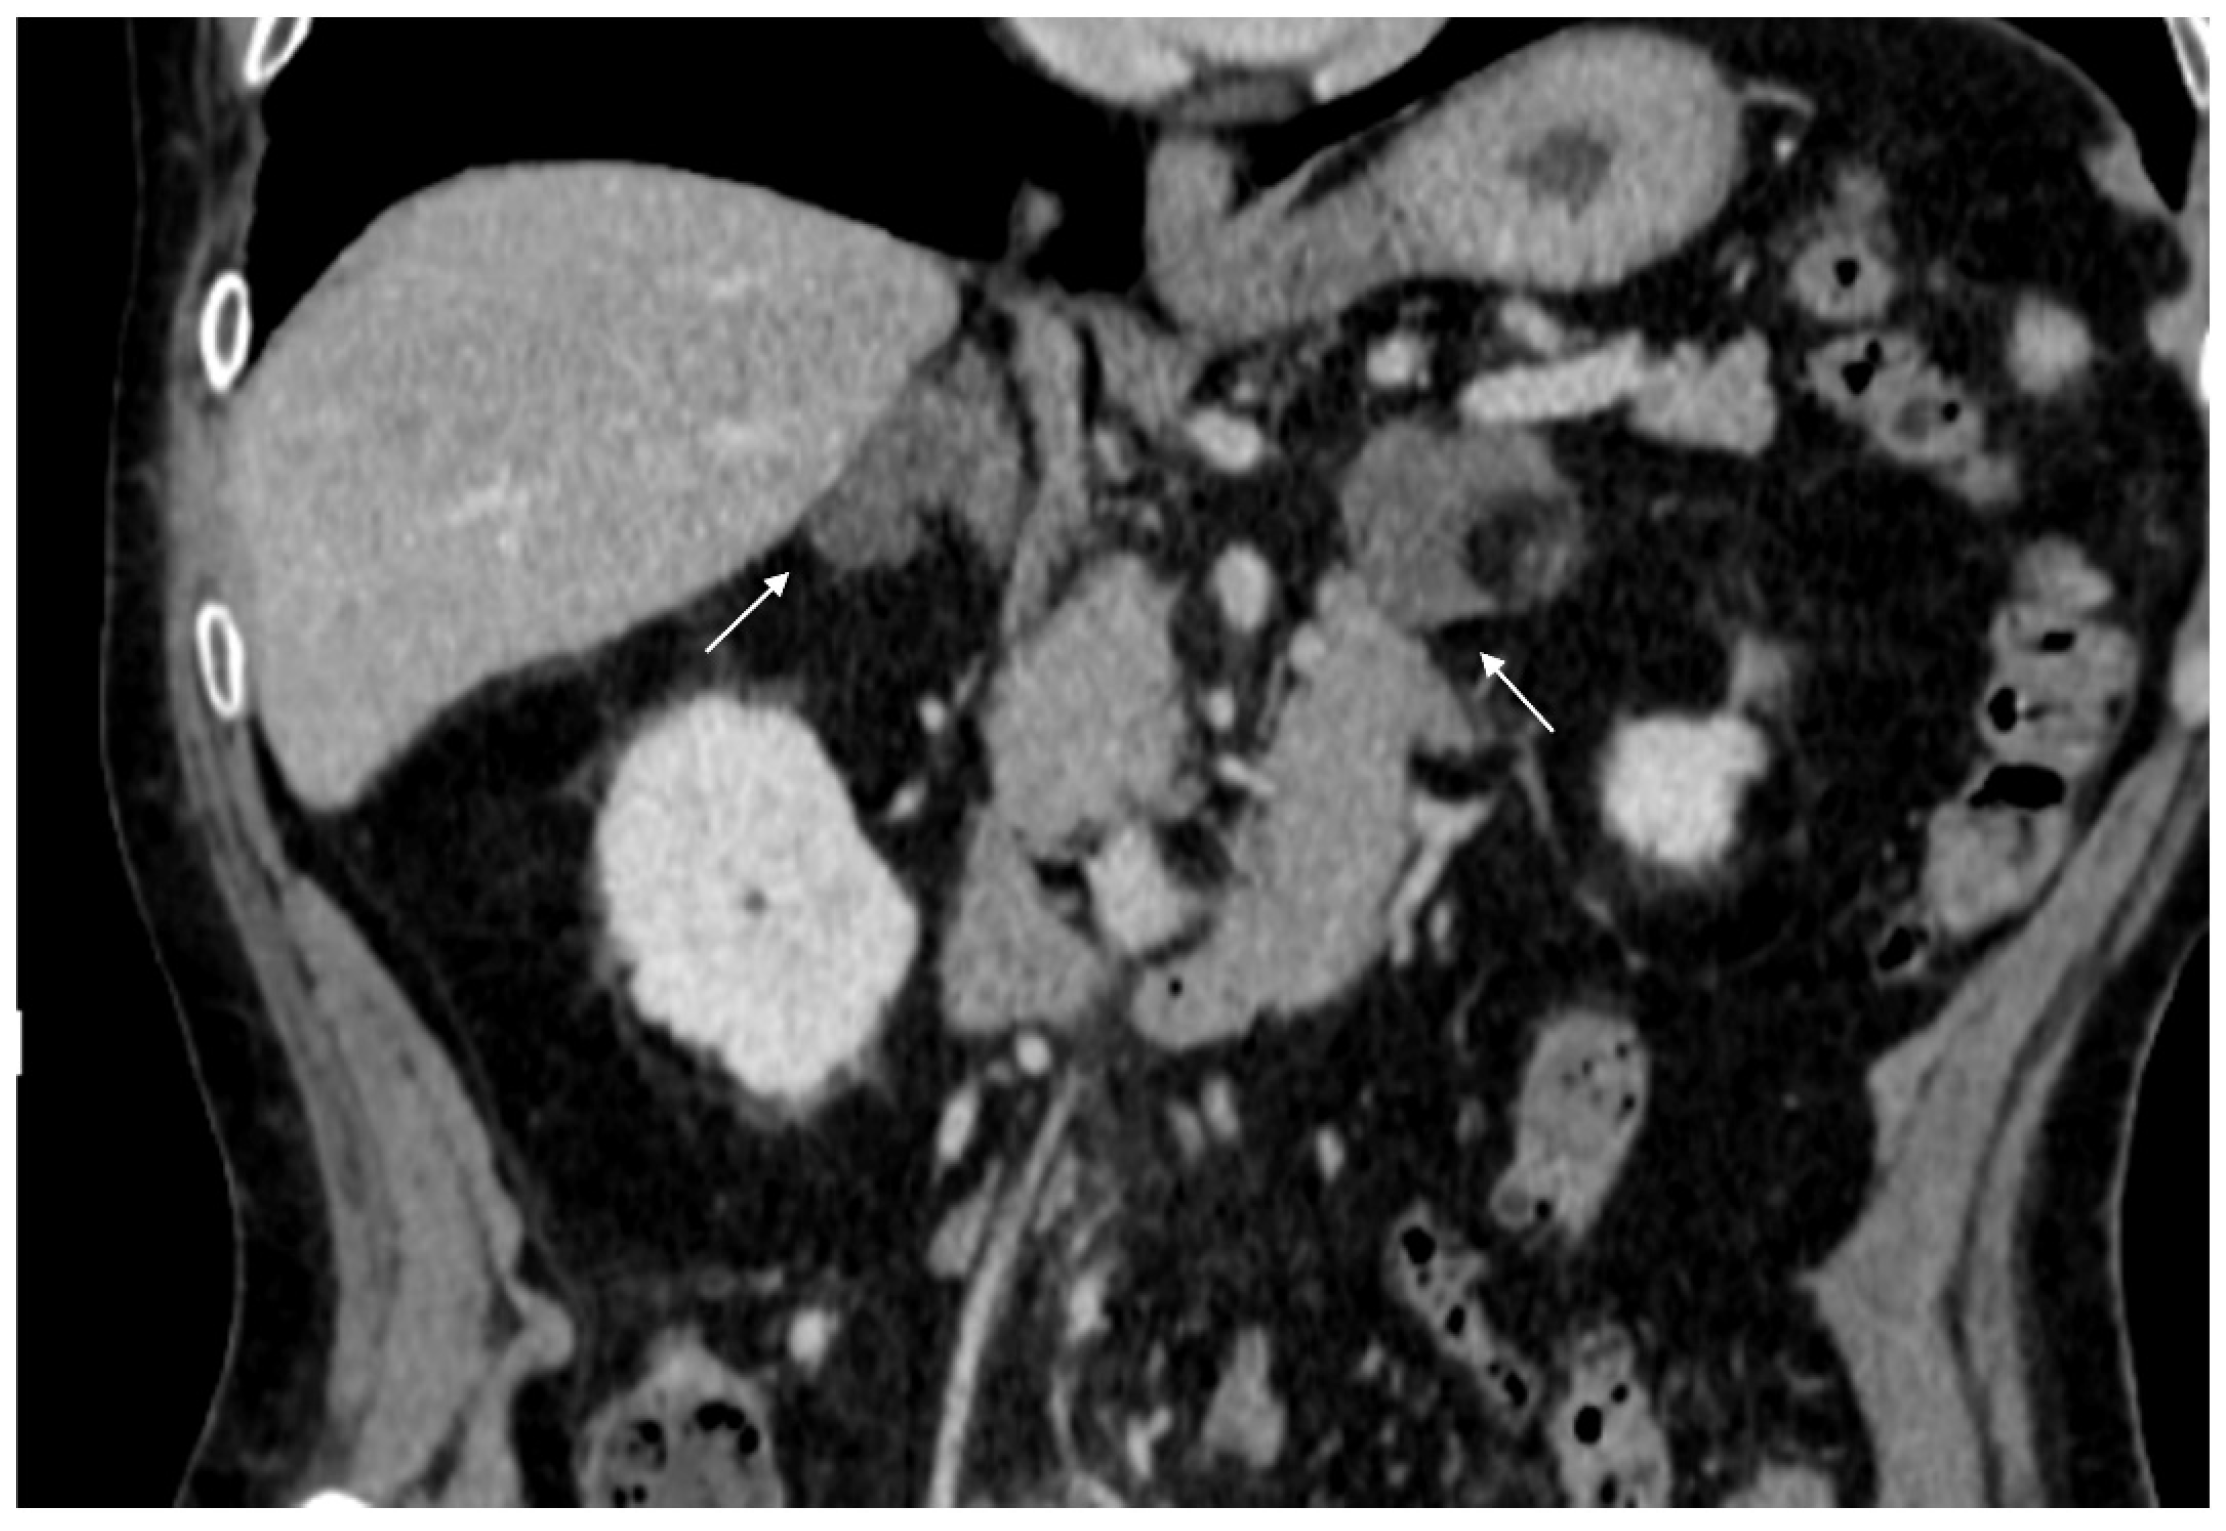

The most common malignant adrenal lesions are metastases, typically originating from lung, breast, stomach, liver, kidney, pancreas, and colon cancers, as well as melanomas and malignant lymphomas (Figure 3) [20]. Alternatively, primary adrenal diseases such as pheochromocytomas or adrenocortical carcinomas (ACC) may be present (Figure 4) [9]. ACC is a rare and aggressive malignant tumor of the adrenal cortex, with a poor prognosis and an incidence of approximately one case per million people per year. The most common clinical manifestation of ACC is cortisol overproduction, observed in up to 40% of cases [21]. Pheochromocytomas are rare, typically benign tumors (90%), though a small percentage may be malignant [22,23]. They are associated with catecholamine production and are evaluated by measuring metanephrine and normetanephrine levels [1,24]. Less common malignant adrenal lesions include lymphomas and neuroblastomas, one of the most common abdominal tumors in children [7,25,26].

Figure 3.

60-year-old woman with history of breast cancer and adrenal metastasis. Left adrenal mass with inhomogeneous enhancement (arrow) on CT portal phase in axial (A) and coronal (B) planes, and positive PET (C).

Figure 4.

36-year-old man with history of night sweats, hypertension, and tachycardia due to pheochromocytoma (arrow). Non-contrast CT shows an inhomogeneous right adrenal mass > 20 HU (A). In the arterial phase (B), the mass shows intense enhancement of the solid components with persistent enhancement. In the late phase (C), absolute contrast medium washout is <50%.